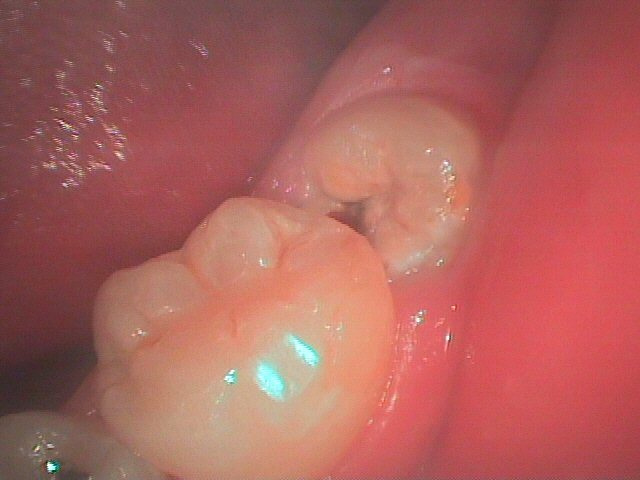

親知らず

横向きなど異常な生え方は磨きにくく、食べかすなどが溜まりやすい為、むし歯や歯肉炎、歯周病になりやすい。

また、手前の歯を押して歯並びを乱し、かみ合わせが悪くなったり、顎関節症の原因になったりします。

(2)完全に生えてなく、歯肉炎を繰り返している。

(4)少しだけ生え、歯ぐきの中に埋まった状態でそれ以上生えてこない。